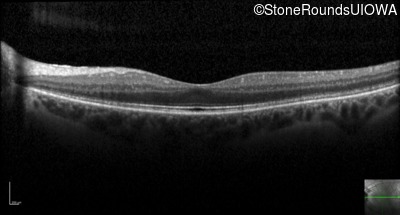

Optical Coherence Tomography - Right - 20/32

Exemplar / OCT Stack

OCT Stack

Optical Coherence Tomography - Left - 20/32